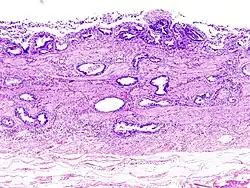

-

Gallbladder adenocarcinoma lymphatic invasion histopathology -

Incidentally discovered gallbladder cancer (adenocarcinoma) following a cholecystectomy. -

Gallbladder adenocarcinoma histopathology -